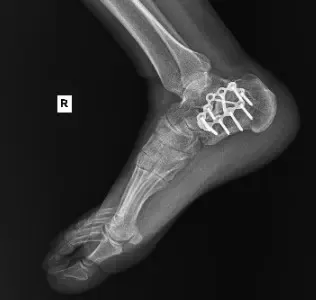

A middle-aged male construction worker presented with persistent right ankle pain and instability following a work-related injury. The patient sustained a right calcaneus fracture after jumping from a collapsing trailer while unloading materials. His injury occurred while working as an ironworker, and he required open reduction and internal fixation (ORIF) of the right heel at a tertiary medical center.

After continued symptoms, imaging revealed:

Post-traumatic subtalar osteoarthritis following calcaneus ORIF

The patient underwent right subtalar arthrodesis with hardware removal at a local medical center. Intraoperatively, significant post-traumatic changes, joint degeneration, and residual deformity were observed. A structural bone graft was placed, and internal fixation was used to achieve stability. The procedure was successfully completed with minimal blood loss.

Follow-up X-rays: Confirmed hardware in situ with robust fusion progression.